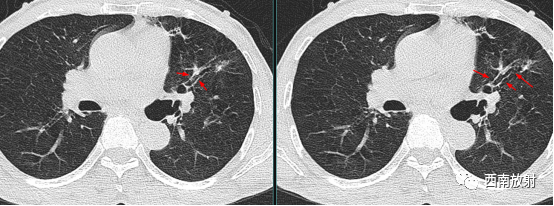

囊状支气管扩张支气管壁内外光滑,呈一串葡萄状,气液平面是其特征性表现;静脉曲张型支气管扩张呈蚯蚓状纡曲,管壁增厚不规则。

▲图:柱状支气管扩张,在扩张的支气管与扫描层面平行时,出现双轨征。